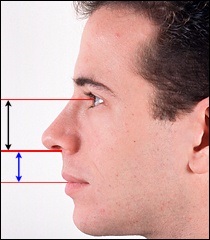

Mielőtt nagyobb acanthion. Ez az, amit úgy néz ki, a művelet során. Az ábrán a jobb ez sárga színű. Acanthion columella található, közvetlenül alatta, ahol a felső ajak határos az alapja az orrát.

Része a gerinc, amelyeket el kell távolítani jelzi a kék vonalon. Removal végezzük vésővel.

Ebben a beteg, ott van a hatás a „kötés” a felső ajak. Photo fenti elégedett üzemeltetés előtt. Fekete jelzi a helyzetét az első kiálló orr-gerinc. A kék vonalat húzott a jobb megítélése a profilt. Ha a hatása „árukapcsolás” a felső ajak vonal irányította a profilját Vered és legfeljebb az alap az orr.

Az operáció utáni képek labrum irányban függőlegesen felfelé.